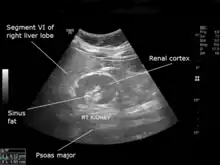

| An ultrasound scan of a hypoplastic right kidney in an adult male. | |

| Diagnostic method | Ultrasound |